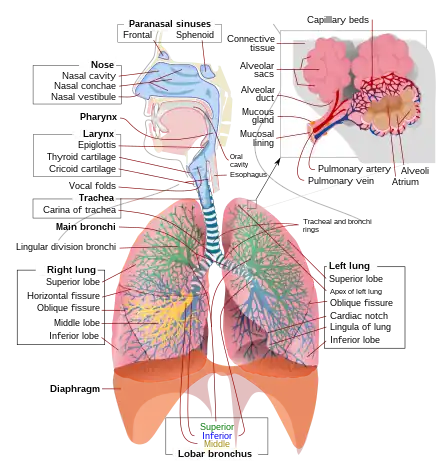

The following are images from various Medicine-related articles on Wikipedia.

Anatomy